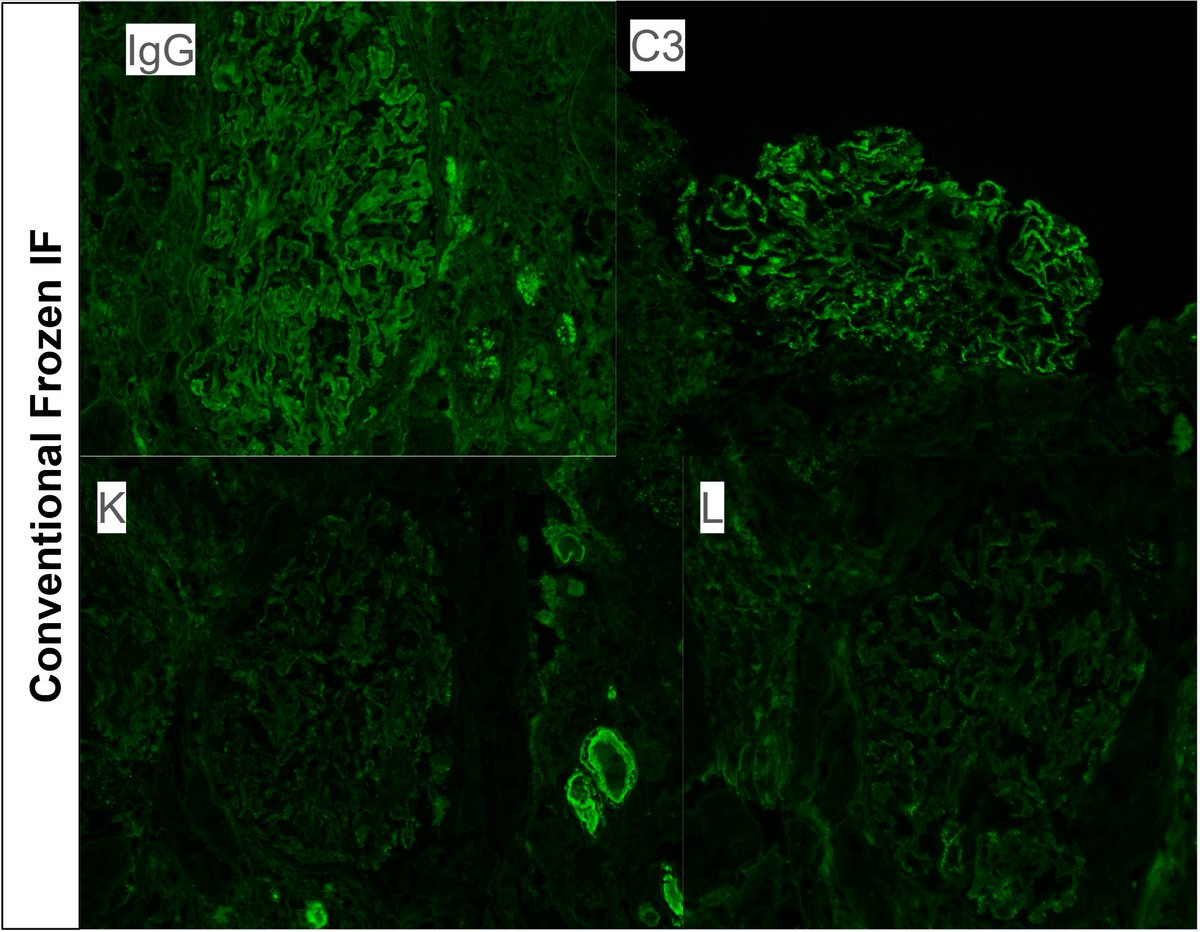

Diagnosis unmasked. Young F with 2g proteinuria, weak +dsDNA. Membranous pattern, IF with C3 dominant staining. Pronase IF --> IgG-k. Membranous-like glomerulopathy with masked monotypic IgG-k deposits. Considered to be autoimmune; not MGRS. #renalpath #pathtwitter #nephrology.

Typically occurs in young women with vague autoimmune history. Has not been associated with MGUS, plasma cell dyscrasias, or lymphomas. Deposits + for SAP. See references here: . https://t.co/CNa8qlPQkb https://t.co/qN4wxgDJp3